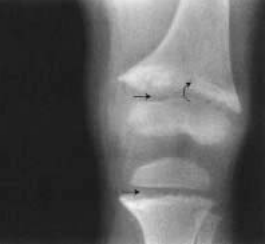

In osteomalacia there is a softening of bone tissue because of lack of formation of calcium salts. Possible causes include deficiency of vitamin D, needed to absorb calcium and phosphorus from the intestine; renal disorders; liver disease; and certain intestinal disorders. When osteomalacia occurs in children, the disease is called rickets (Fig. 2). Rickets is usually caused by a deficiency of vitamin D.

FIGURE 2. Rickets. Radiograph of the left knee joint showing widening of the growth regions of the bones (arrows). (Reprinted with permission from Erkonen WE, Smith WL. Radiology 101: Basics and Fundamentals of Imaging. Philadelphia: Lippincott Williams & Wilkins, 1998.)